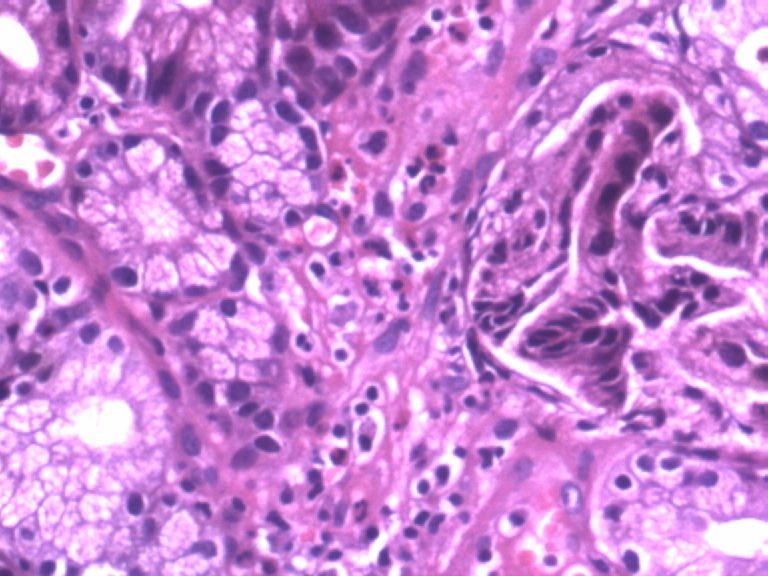

男,50岁,胃镜活检食管下段溃疡组织3块。

从图片看,应该是贲门部位的组织,显示急性炎症改变,腺体结构稍有不规则,可能为炎性刺激所致,总之未见肿瘤性病变。

贲门粘膜炎伴上皮轻度不典型增生。

图示急性炎症,炎症累及上皮,腺细胞反应性增生。

倾向良性,腺体形态的改变符合炎症修复所致。

腺体有轻度异型,未见粘膜下浸润,应报“低级别上皮内瘤变”。建议重取材或密切随访。